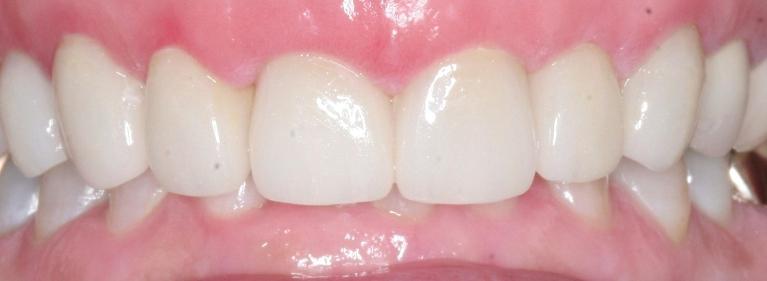

Once we are satisfied that there is no longer any sign of infection, we fill the tooth using a special sealant. A crown is placed over the exterior of the tooth to restore the functioning of the tooth and prevent further damage.

Thanks to CEREC technology, the crown can be created right here in our office and placed on the same day, eliminating the need for a return trip to the dentist. In addition, your crown is customized to perfectly match your own teeth, so it looks and functions just like a normal tooth.